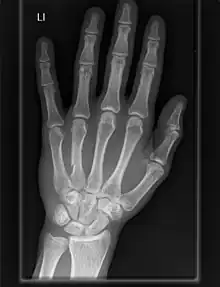

The carpometacarpal (CMC) joints are five joints in the wrist that articulate the distal row of carpal bones and the proximal bases of the five metacarpal bones.

The CMC joint of the thumb or the first CMC joint, also known as the trapeziometacarpal (TMC) joint, differs significantly from the other four CMC joints and is therefore described separately.

Fingers

- The second metacarpal articulates primarily with the trapezoid and secondarily with the trapezium and capitate.

- The third metacarpal articulates primarily with the capitate,

- The fourth metacarpal articulates with the capitate and hamate.

- The fifth metacarpal articulates with the hamate.

Among themselves, the four ulnar metacarpals also articulates with their neighbours at the intermetacarpal articulations.[7]